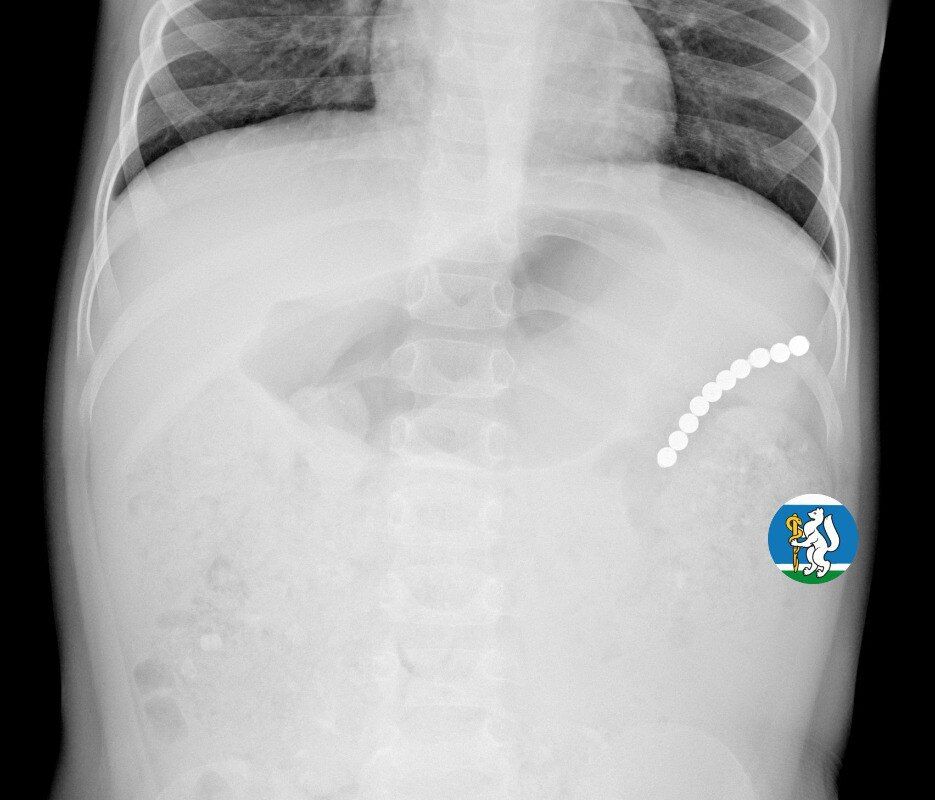

Девочка рассказала родителям о плохом самочувствии, и те показали ее врачам. Медики направили пациентку на рентген грудной клетки. Благодаря обследованию специалисты обнаружили в проекции желудка цепочку магнитов, соединенных между собой. Ребенку сразу же госпитализировали и оказали помощь.

«Для минимизации риска осложнений удаление инородных тел было проведено интраоперационно. В ходе вмешательства дежурная бригада врачей извлекла 10 магнитных шариков, цепочка которых в длину составила 5 сантиметров», — рассказал детский хирург ДГКБ №9 Андрей Чукреев.